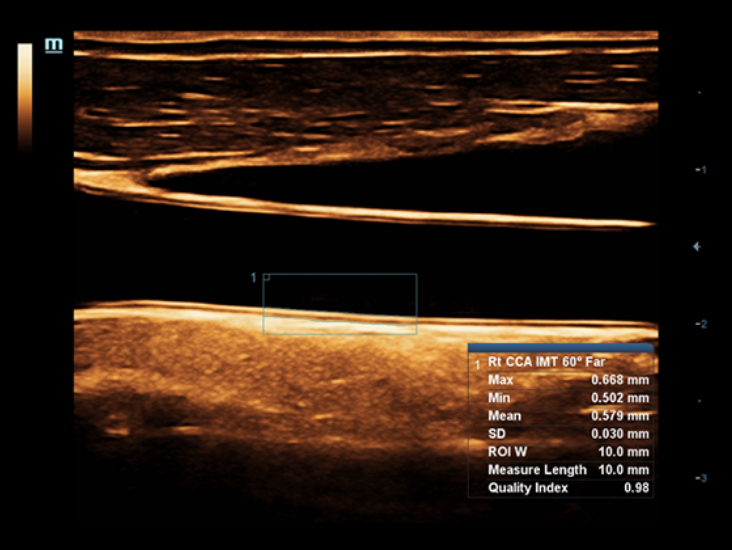

Klinische Bilder